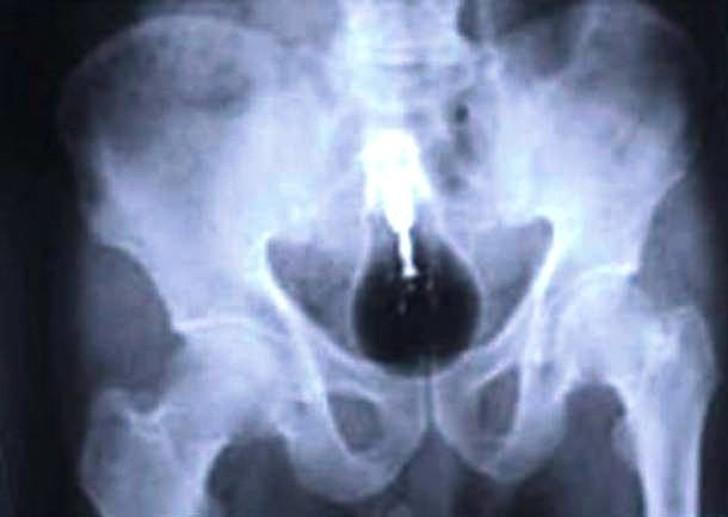

2. Пуля.